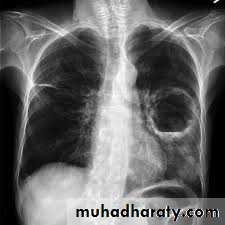

Slide 41- What is the finding in this x ray?2- Give 2 deferential diagnoses